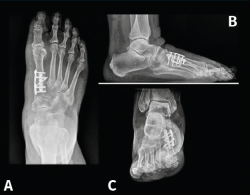

El año 2017 A. Isidro y A. Malgosa(2) publicaron un caso de gran interés perteneciente a la necrópolis de Sharuna (Egipto Medio); correspondía al HV de una momia con la cápsula articular y el complejo ligamentoso asociado preservados. En esta misma necrópolis, de un total de 631 individuos estudiados, se pudieron observar 3 casos de HV. Los 3 individuos fueron datados a finales de la VI Dinastía (Reino Antiguo; aprox. 2.200 a. C.). En la necrópolis copta inicial de Qarara (ss. IV al VII d. C.), situada a unos escasos 20 km al norte del anterior yacimiento, se pudo objetivar mediante una radiografía de un pie, en proyección dorsoplantar, la presencia de un HV en un primer radio parcialmente momificado (Figura 1).

Figura 1. Hallux valgus de un individuo procedente de la necrópolis de Qarara (Egipto Medio, periodo copto inicial, ss. IV a VII d. C.). A: visión plantar donde se aprecian los sesamoideos y restos del tendón flexor hallucis longus; B: visión dorsal; C: radiografía en proyección dorsoplantar tomada in situ en la cual puede verse el complejo periarticular preservado, así como la deformidad en hallux valgus.